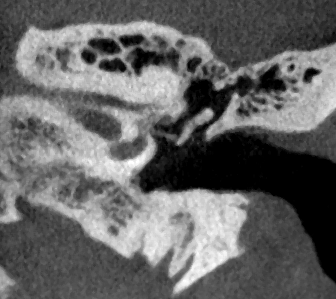

Bilder Ohr

Ambossarrosion mit Stapesprothese Stapesprothese Teflon (Causse) PORP auf Stapes PORP Titan auf Stapes PORP PORP Titan disloziiert Otosklerose Otoskleroseherd TORP Pauke nicht belüftet TORP unter Knorpelinsel disl.